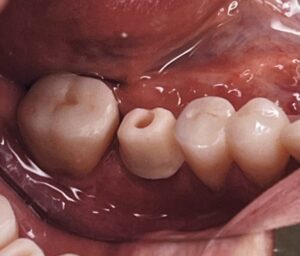

今回の写真は、奥歯に一本インプラント体を入れた治療例ですが、治療計画から三ヶ月もあればこのような歯を入れることができます。

実際にはインプラントの上に金属の土台をねじ止めしたり、歯茎のキワにはプラークがつきにくい特徴をいかして、ジルコニアを立ち上げに使い、何かあった時に上の部分だけ外せるよう、その上にさらにジルコニアのクラウンを被せています。